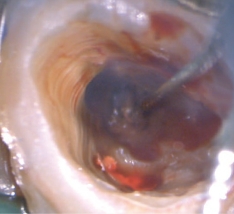

HFC(High Frequency Conduction:高周波通電)

高周波通電により、チップ電極の先端部と接触した部位を発熱させることで、組織の焼灼・凝固・切開を行うことができます。

根管長測定機能によって根管内のチップ電極の位置を設定し、フットスイッチを踏むことで1秒間のHFCが行えます。

また、麻酔が難しい場合を想定した、小出力の分割通電モードも搭載しています。

2タイプのチップ電極を付属。どちらでも根管長測定、HFCが行えます。

チップ電極(ファイルタイプ) -

チップ電極(エンドファイルタイプ)

マイクロスコープ利用時の術野確保に有効です。